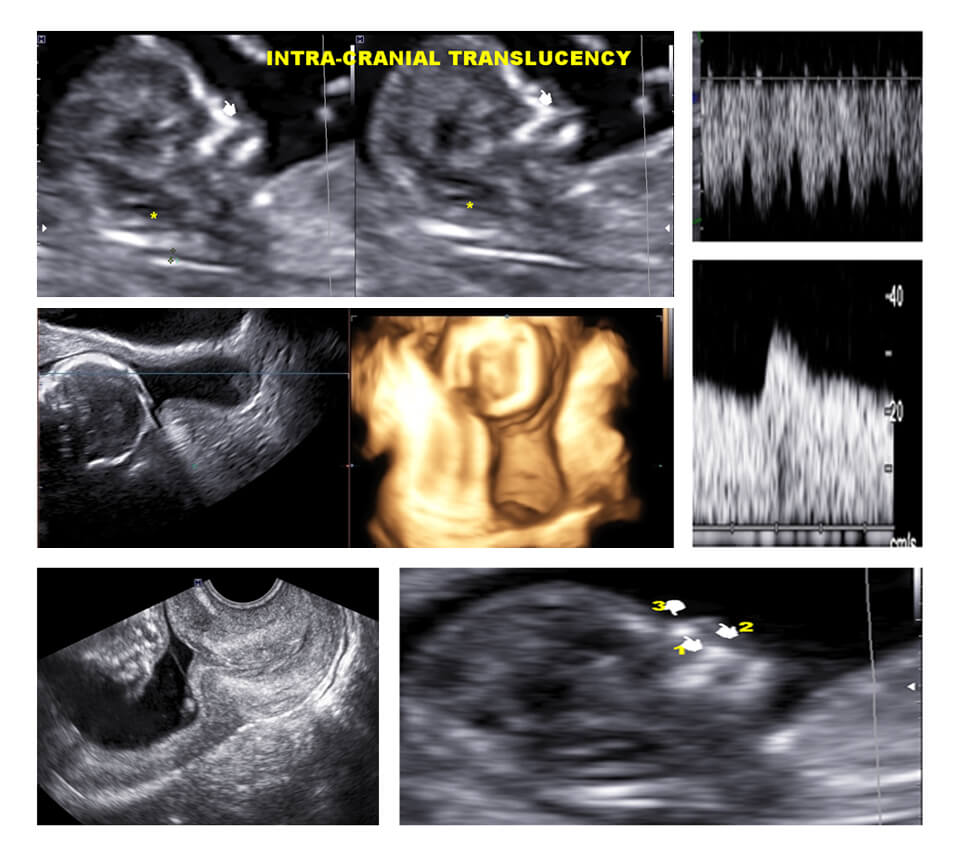

MODULE 5 :- 11-14 WEEKS PREGNANCY

10-14 WEEKS: SCREENING STRATEGIES AND WORKUP, 10-14 WEEKS: FETAL ANATOMY N STRUCTURAL DEFECTS (EYE OPENER)